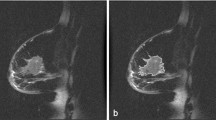

A total of 5178 radiomic features from the T1+C, T2WI, and DWI-ADC sequences of both the tumoral VOI and peritumoral VOI of each patient’s MRI were extracted and analyzed, as shown in Fig. 2 and listed in electronic supplementary Table S1. Using the Mann–Whitney U test, we coarsely selected imaging features with a p-value <0.05 between pCR and non-pCR patients. The RF algorithm was used to rank the above selected features and the top 30 features of each sequence were selected. The top 20 and top 30 key radiomic features were used for further single-sequence SVM model construction. The optimal number of features was determined as top 30 for better performance (electronic supplementary Table S3). The classification of these features is shown in electronic supplementary Table S4.

Radiomics workflow. a T1+C, T2WI, and DWI-ADC sequences of multiparametric MRI images were recruited for analysis. b Tumoral and peritumoral ROIs were identified and segmented slice by slice on T1+C sequence, and ROIs were respectively synthesized into 3D VOIs automatically using software. VOIs were copied to two other sequences for the next analysis. c The features of each sequence and each VOI were extracted using 3D Slicer software, including shape, intensity, texture, and wavelet features. d Random forest algorithm and support vector machine methods were mainly used for key features selection and radiomic model construction. T1+C contrast-enhanced T1-weighted imaging, T2WI T2-weighted imaging, DWI-ADC diffusion-weighted imaging quantitatively measured the apparent diffusion coefficient, MRI magnetic resonance imaging, ROI region of interest, VOI volume of interest, 3D three-dimensional